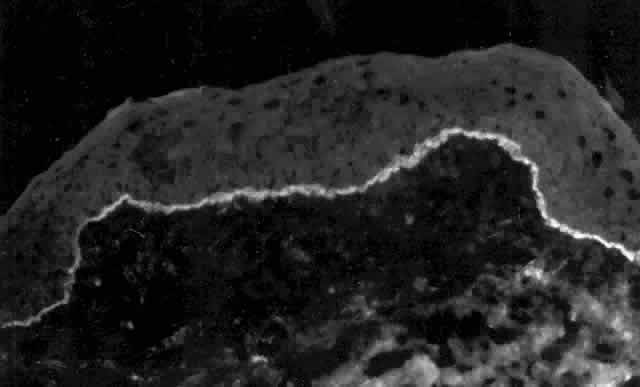

Pemphigus can be differentiated from bullous pemphigoid and from cicatricial pemphigoid on histologic and immunologic bases. Whereas the bullae in pemphigus are intraepidermal, those occurring in bullous pemphigoid and in cicatricial pemphigoid are subepidermal, between epidermis and dermis, or between mucosa and submucosa. Acantholysis is not present in the latter two conditions.5 In bullous pemphigoid and in cicatricial pemphigoid there are tissue-fixed immunoglobulins in the subepidermal basement membrane zone (Fig. 2).11 This is in contrast to the interepidermal fixation of antibodies (Fig. 3) seen in pemphigus (Table 1).

Fig. 2. Fluorescence microscopy of conjunctiva from a patient with cicatricial pemphigoid affecting the eye. The antibody used was a fluorescein-conjugated antibody directed against human IgG. Note the bright, continuous, linear deposition of IgG at the epithelial basement membrane zone, a finding virtually diagnostic of cicatricial pemphigoid.